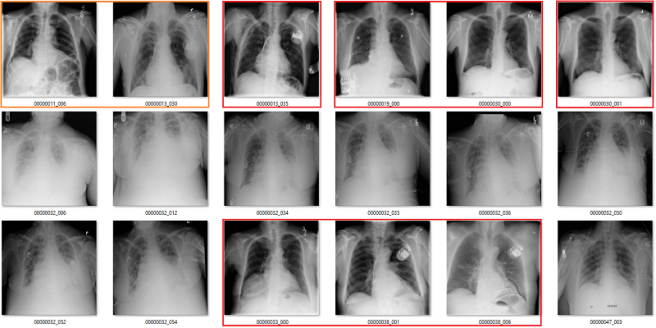

What follows is a bunch of pictures based on the labels in the dataset. In this case, they are pseudo-random. Like I said, it doesn’t have to be perfect. They are randomly chosen sequential sets of 18 images. They are not cherry-picked.

Also, I have tried to err on the side of caution, in the sense that I favour the label class when a case is equivocal.

In all the images, red = clearly wrong label. Orange = I doubt it, I wouldn’t report it, but I can’t really exclude it. Correlate clinically :p

Atelectasis

My labels aren’t perfect. Other radiologists will disagree with some of them, and the reduced resolution doesn’t help. But it should be clear that my labels and the results presented in the paper/supplement are vastly different.

I always like hard numbers, so I did my best to quantify the label accuracy where I can. I actually found it very hard to define many of the labels, which is why they are not listed below. I reviewed ~130 images in each class, and calculated the accuracy of the original labels according to my visual interpretation. This is a pretty good amount of data to use, as the 95% confidence intervals will probably be less than +/- 5%, even allowing myself up to a 20% error rate.

Visual analysis by me. Text mining results from the paper.

Again, I doubt my labels are “right” compared to some form of fairly reliable ground truth (like a panel of chest radiologists), but the difference here is stark. I think that these findings make a strong case that these labels do not appear to visually match the diseases they should represent.